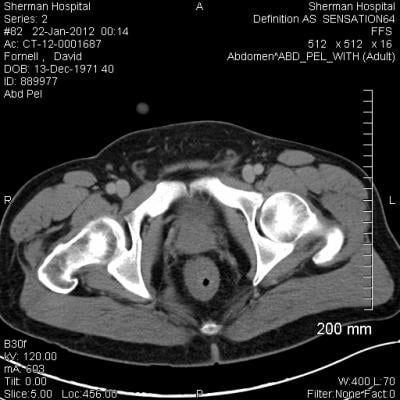

Ct Scan Of The Abdomen Reveals A Uterus U With Dilated Cavity Arrow Download Scientific Diagram